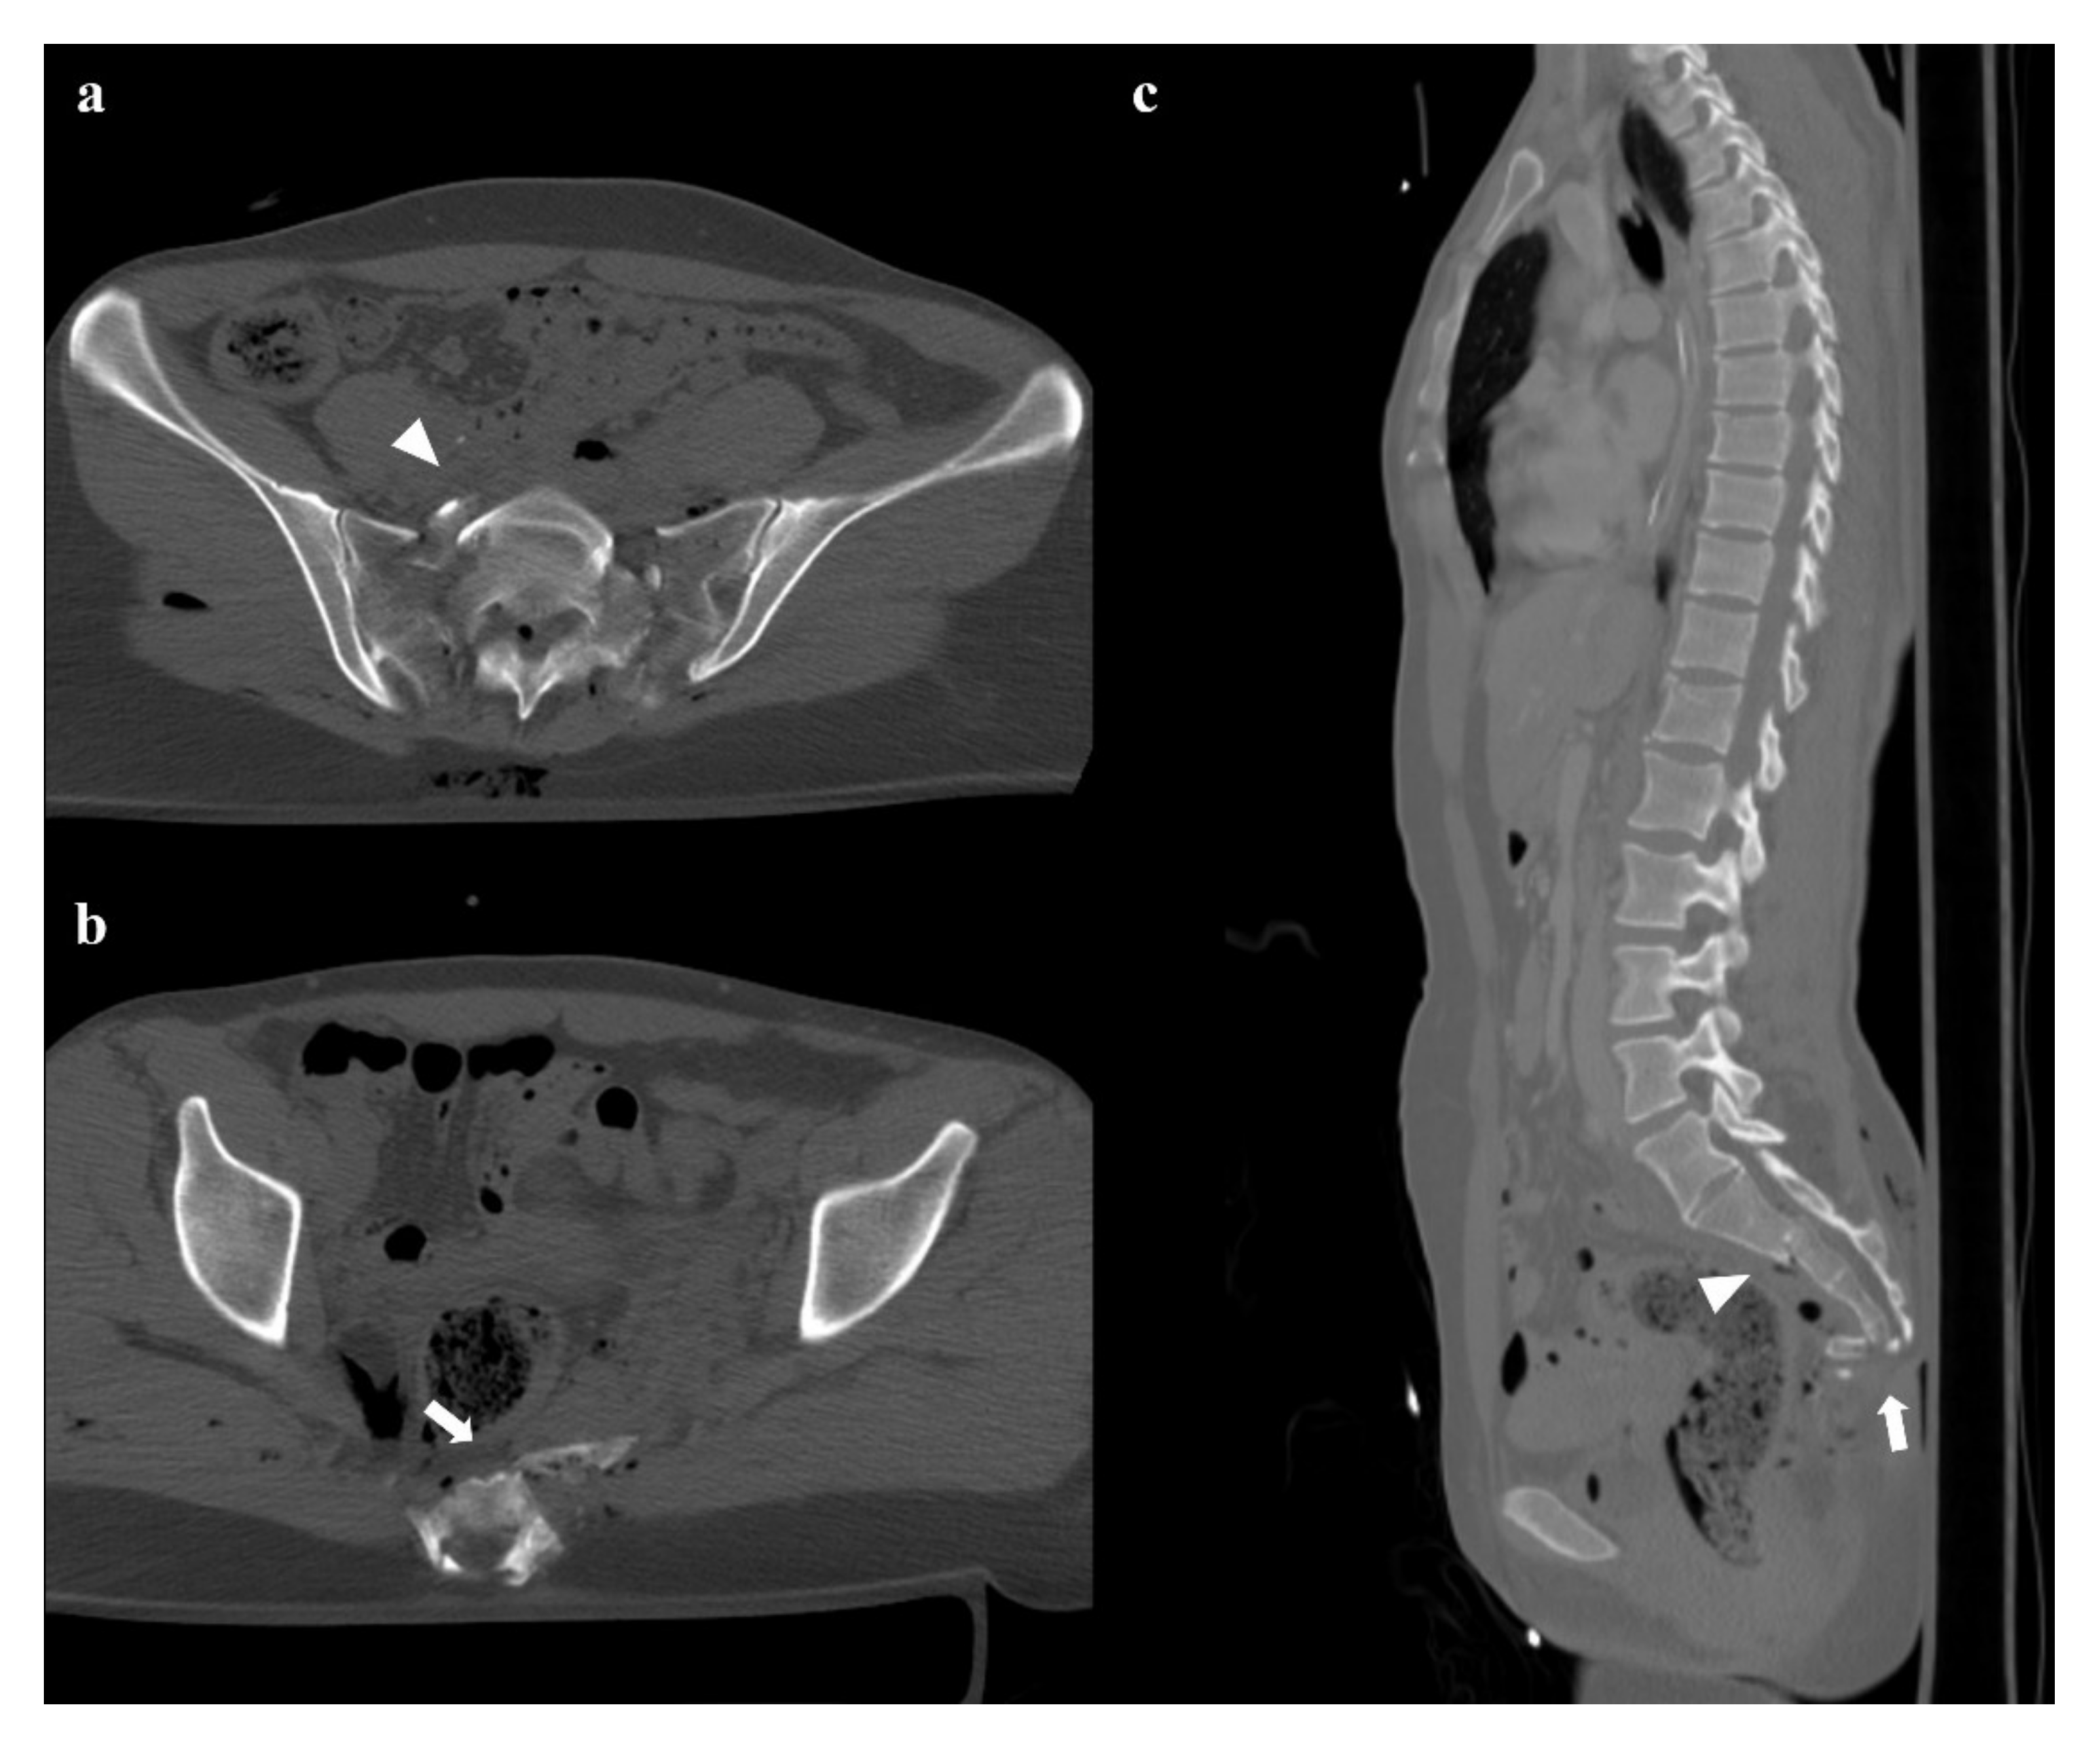

- Zone III: the fracture is medial to the neuroforamina and involves the central canal. A combined fracture in this zone may have different morphology (“H”-shaped, “U”-shaped, “λ”-shaped, “T”-shaped), and can result in a spinopelvic dissociation (Figure 8). Zone III fractures can also be divided into four additional groups: anterior angulation of the fracture without dislocation (type 1), anterior angulation of the fracture with retrolisthesis (type 2), complete anterolisthesis of the fracture fragments (type 3), and comminuted fracture of S1 or S2 (type 4) [22]. In zone III fractures, there is a neurological injury in 56% of cases, with bowel and genitourinary dysfunction [8].

- Type A: an injury of lower sacrococcygeal spine, below the level of the sacroiliac joint. These fractures have no impact on the spinopelvic stability.

- Type B: a posterior pelvic fracture, characterized by a unilateral vertical sacral fracture. In these fractures, the posterior pelvic stability may be compromised.

- Type C: spinopelvic fractures, which are unstable.